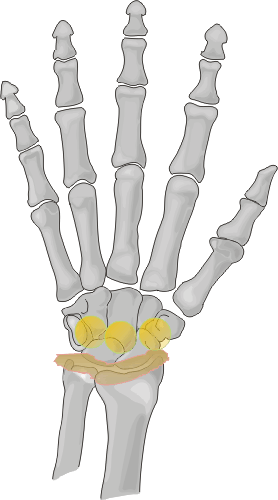

Silastic arthropathy can occur at any of the bones where there is a prosthetic

implant in place. However, involvement at the hand and wrist is most common

at the carpal bones, a location that is more susceptible to stress forces.

In decreasing order of frequency, scaphoid, lunate and scapholunate implants

are the most commonly affected carpal prostheses.